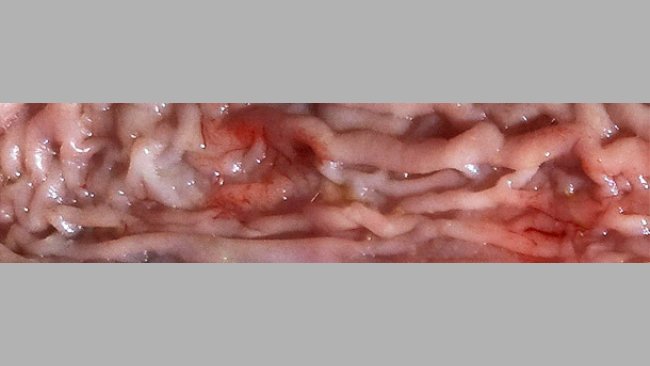

Respuestas sobre pleuroneumonía por App (2/2): diagnóstico, monitorización y erradicación

En este segundo articulo Antonio Vela, Francisco José Pallarés y David Espigares nos responden a preguntas sobre diagnóstico, monitorización y erradicación de la pleuroneumonía causada por Actinobacillus pleuropneumoniae (App).